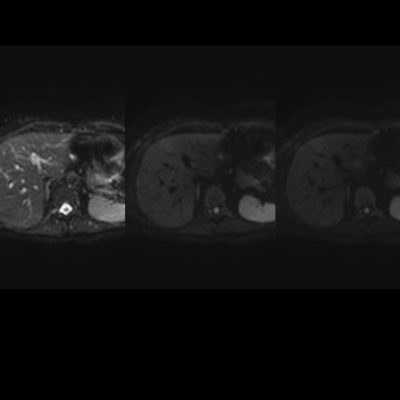

En estos casos se recomienda realizar RM para confirmar la presencia de grasa en las “lesiones” identificadas y descartar otras etiologías, demostrando disminución de la señal en secuencias fuera de fase, sin alteración del pulso difusión (fig. 12 y 13).

Independiente de su patrón de presentación, no condicionan cambios del parénquima luego de la administración de contraste endovenoso, no obstante igualmente se utiliza el gadolinio como medio de contraste para descartar otras entidades que puedan simular esta patología. La TC no suele aportar datos concluyentes cuando los focos de esteatosis son de pequeño tamaño y de bajo contenido graso, no logrando una adecuada diferenciación en su atenuación.7-8 (fig. 14)